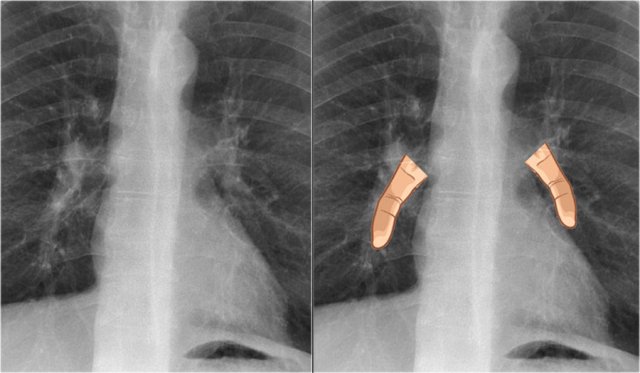

Vena azygos lobe

A common normal variant is the azygos lobe.

The azygos lobe is created when a laterally displaced azygos vein makes a deep fissure in the upper part of the lung.

On a chest film it is seen as a fine line that crosses the apex of the right lung.

Here another patient with an azygos lobe.

The azygos vein is seen as a thick structure within the azygos fissure.